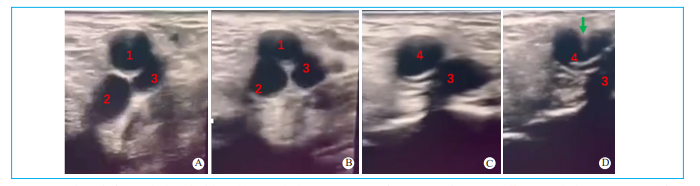

在血管超声引导下进行股动脉穿刺具有极好的安全性和便捷性[16-17],位置更准确,能够避开钙化与狭窄,提高ProGlided成功率,有效减少穿刺并发症和大鞘植入前后的入路并发症。采用超声平面外引导方式,应用线阵血管探头定位血管前壁中点,采用穿刺针进行穿刺,穿刺植入导丝后可以通过超声确认穿刺的准确性(图2)。

超声引导穿刺步骤与技巧:①穿刺前,用水湿润皮肤,使探头与皮肤之间没有气体,保证超声视野的清晰性。②若在局部麻醉下穿刺,穿刺前不宜注射过多的利多卡因,以防止影响穿刺视野,可穿刺成功后补充利多卡因。③深压和轻抬超声探头以便识别股动脉和股静脉,股静脉往往会被完全压瘪,而动脉往往不会完全压瘪,并且动脉具有搏动性;也可采用彩色血流显示和区分动静脉。④选择目标血管时,超声探头正切血管,注意右腿和左腿穿刺时探头角度有所不同,左右滑动超声探头,将目标血管呈现在超声显示屏正中,沿着血管的长轴缓慢移动,明确股总动脉分叉(图2),确保看到股浅动脉和股深动脉汇合成股总动脉的过程,并避开血管壁钙化和狭窄(图3),选择合适的动脉穿刺点。⑤穿刺时,穿刺针从探头正中间进针,并且进针距离探头一般为3~5mm,根据患者胖瘦程度适当调整,可轻轻上下推送穿刺针使血管上方组织随之移动,观察进针方向是否位于动脉的正上方(图2D)。⑥置入临时起搏器需要建立静脉穿刺入路。股静脉往往位于股动脉的内侧和下方,因此股静脉穿刺时,要在探头的偏内侧进针,可以顺着静脉长轴方向移动,找到静脉与动脉内外分开最宽的位置,进针后保持一定负压回抽趋势。

图2 右股总动脉经血管超声引导穿刺  A.血管探头探及股浅动脉和股深动脉以及股静脉;B.血管探头探及股浅动脉和股深动脉汇聚成股总动脉;C.血管探头探及股总动脉以及股静脉;D.血管探头探及穿刺针穿刺股总动脉前壁的正上方。1为右股浅动脉;2为右股深动脉;3为股静脉;4为右股总静脉;绿色箭头为穿刺针从右股总动脉前壁正上方刺入。